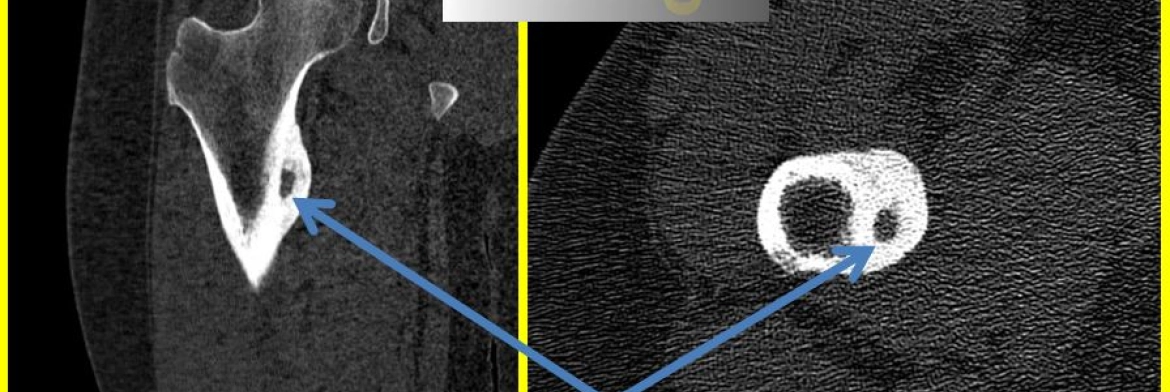

Bilgisayarlı Tomografi (BT): Osteoid osteoma tanısı koymada en değerli görünütleme yöntemi Bilgisayarlı Tomografidir. Lezyonun ortasında ‘’Nidus’’ adı verilen litik yapıdaki lezyon net değerlendirilir.